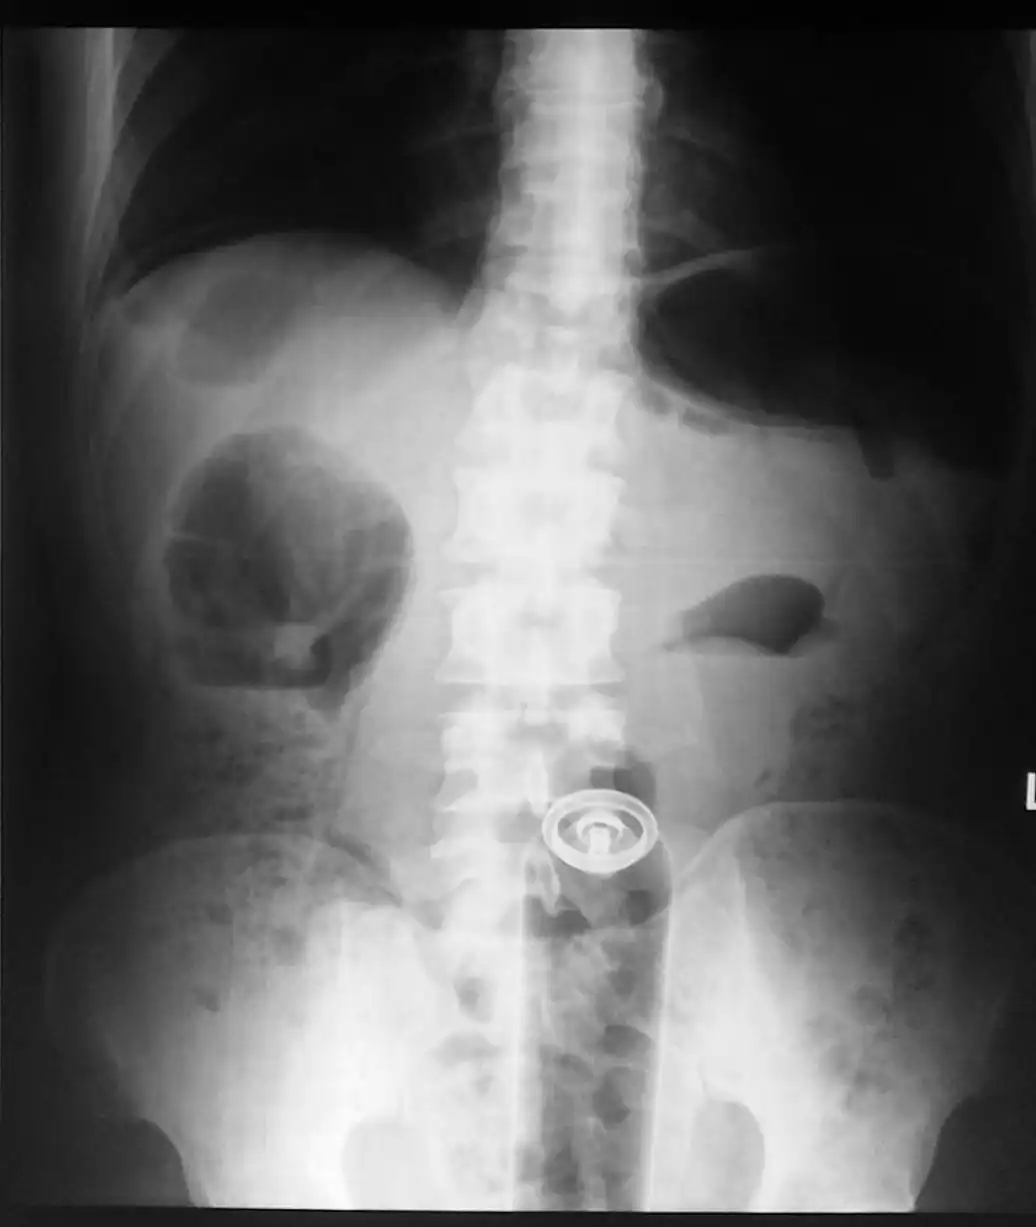

Врачебные находки в интимных местах

Или как впихнуть невпихуемое :lol: